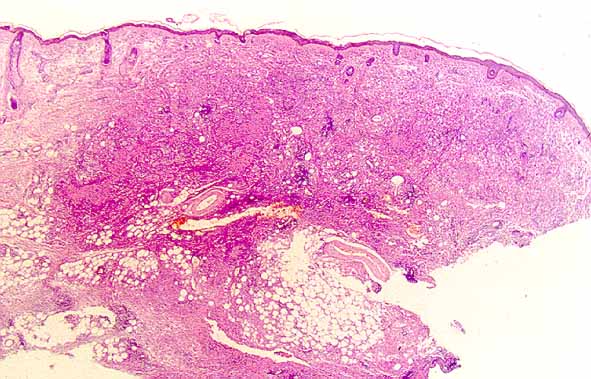

XANTOGRANULOMA NECROBIOTICO.

Una rara lesión cutanea asociada a alteraciones sistémicas

Figura 1 |